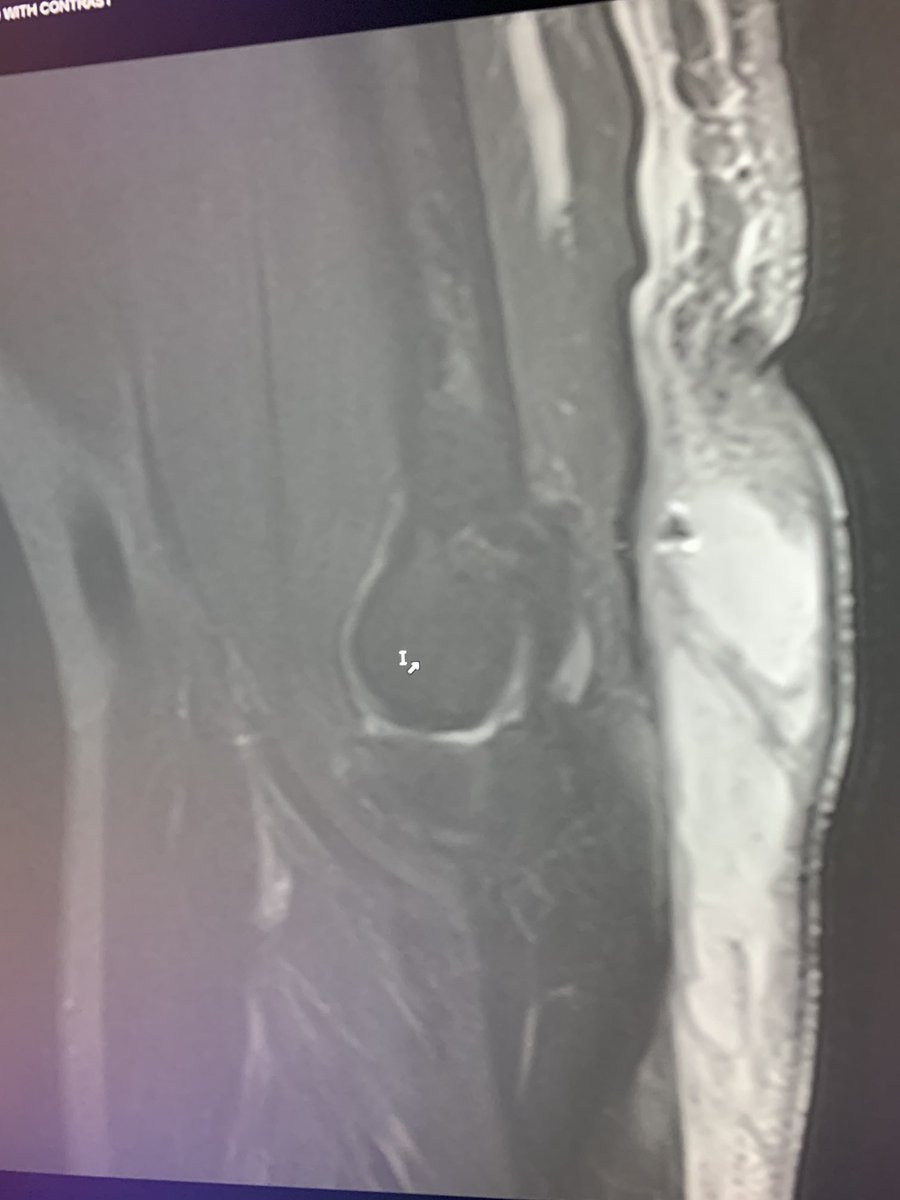

Started out as a minor olecranon bursitis but then someone decided to stick a needle in it and inject steroid early on. Now it’s turned into a monster cellulitis, expansion of bursitis and trying to form an abscess.